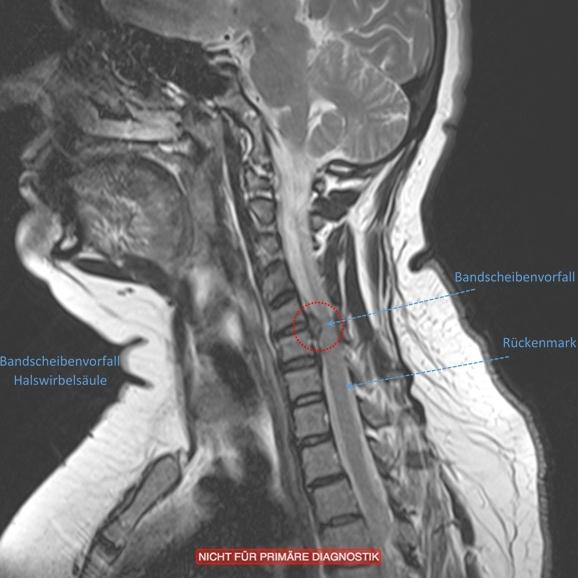

Drückt ein Bandscheibenvorfall auf das Rückenmark (Bandscheibenvorfälle in der Halswirbelsäule), kann dieses geschädigt werden (Myelopathie). Typische Symptome betreffen beide Beine und sind Gangunsicherheit, Taubheit und Kraftminderung. Schmerzen spielen keine oder eine untergeordnete Rolle.. Made in America starts right here with you, your project, and Remarc Manufacturing! Since 1979 Remarc Manufacturing has been operating in Reno Nevada providing premier manufacturing and machining services. We are the only shop in Northern Nevada with CNC machining, Water Jet cutting, manual machining Welding, Inspection, and a large inventory.

Zervikaler Bandscheibenvorfall, Bandscheibenvorfall der Halswirbelsäule